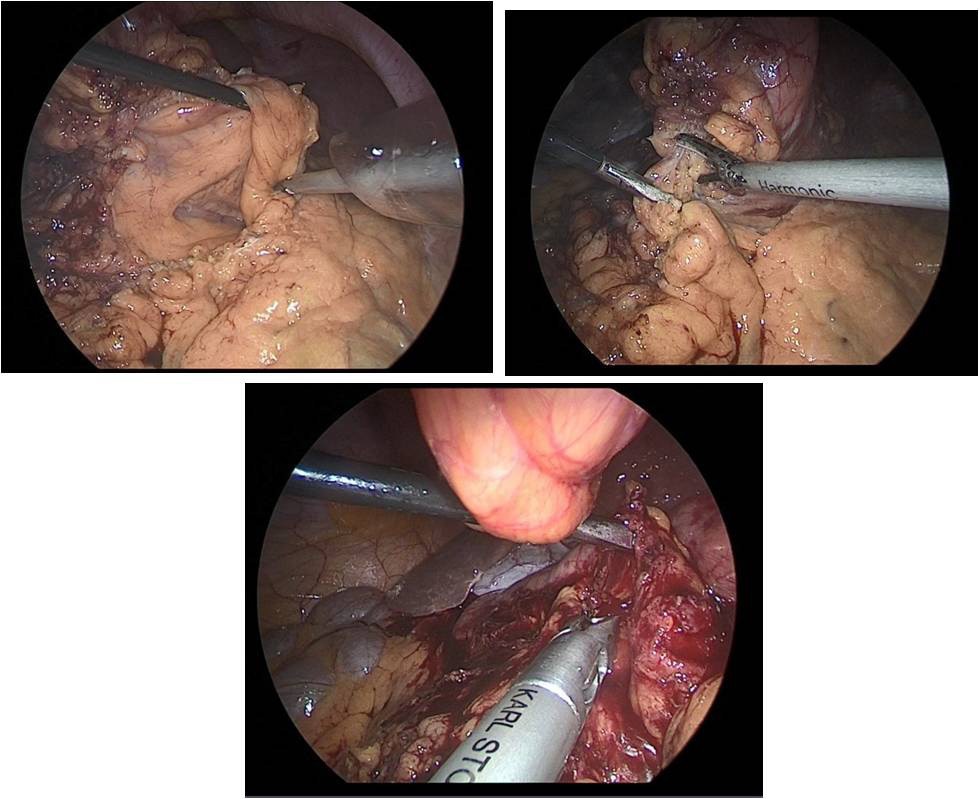

Then performed resection of the greater omentum with lymph dissection II, IV, VI groups of lymph nodes (Figure 10a,b).

Figure 10a,b: Laparoscopic omentectomy.

Figure 11a,b: Laparoscopic omentectomy.